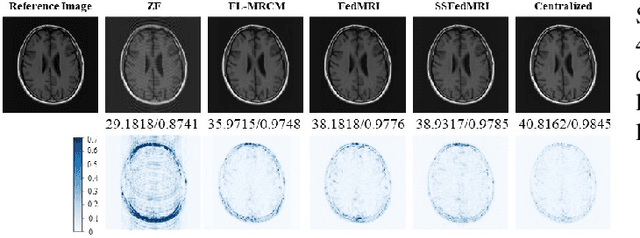

Federated learning (FL) based magnetic resonance (MR) image reconstruction can facilitate learning valuable priors from multi-site institutions without violating patient's privacy for accelerating MR imaging. However, existing methods rely on fully sampled data for collaborative training of the model. The client that only possesses undersampled data can neither participate in FL nor benefit from other clients. Furthermore, heterogeneous data distributions hinder FL from training an effective deep learning reconstruction model and thus cause performance degradation. To address these issues, we propose a Self-Supervised Federated Learning method (SSFedMRI). SSFedMRI explores the physics-based contrastive reconstruction networks in each client to realize cross-site collaborative training in the absence of fully sampled data. Furthermore, a personalized soft update scheme is designed to simultaneously capture the global shared representations among different centers and maintain the specific data distribution of each client. The proposed method is evaluated on four datasets and compared to the latest state-of-the-art approaches. Experimental results demonstrate that SSFedMRI possesses strong capability in reconstructing accurate MR images both visually and quantitatively on both in-distribution and out-of-distribution datasets.